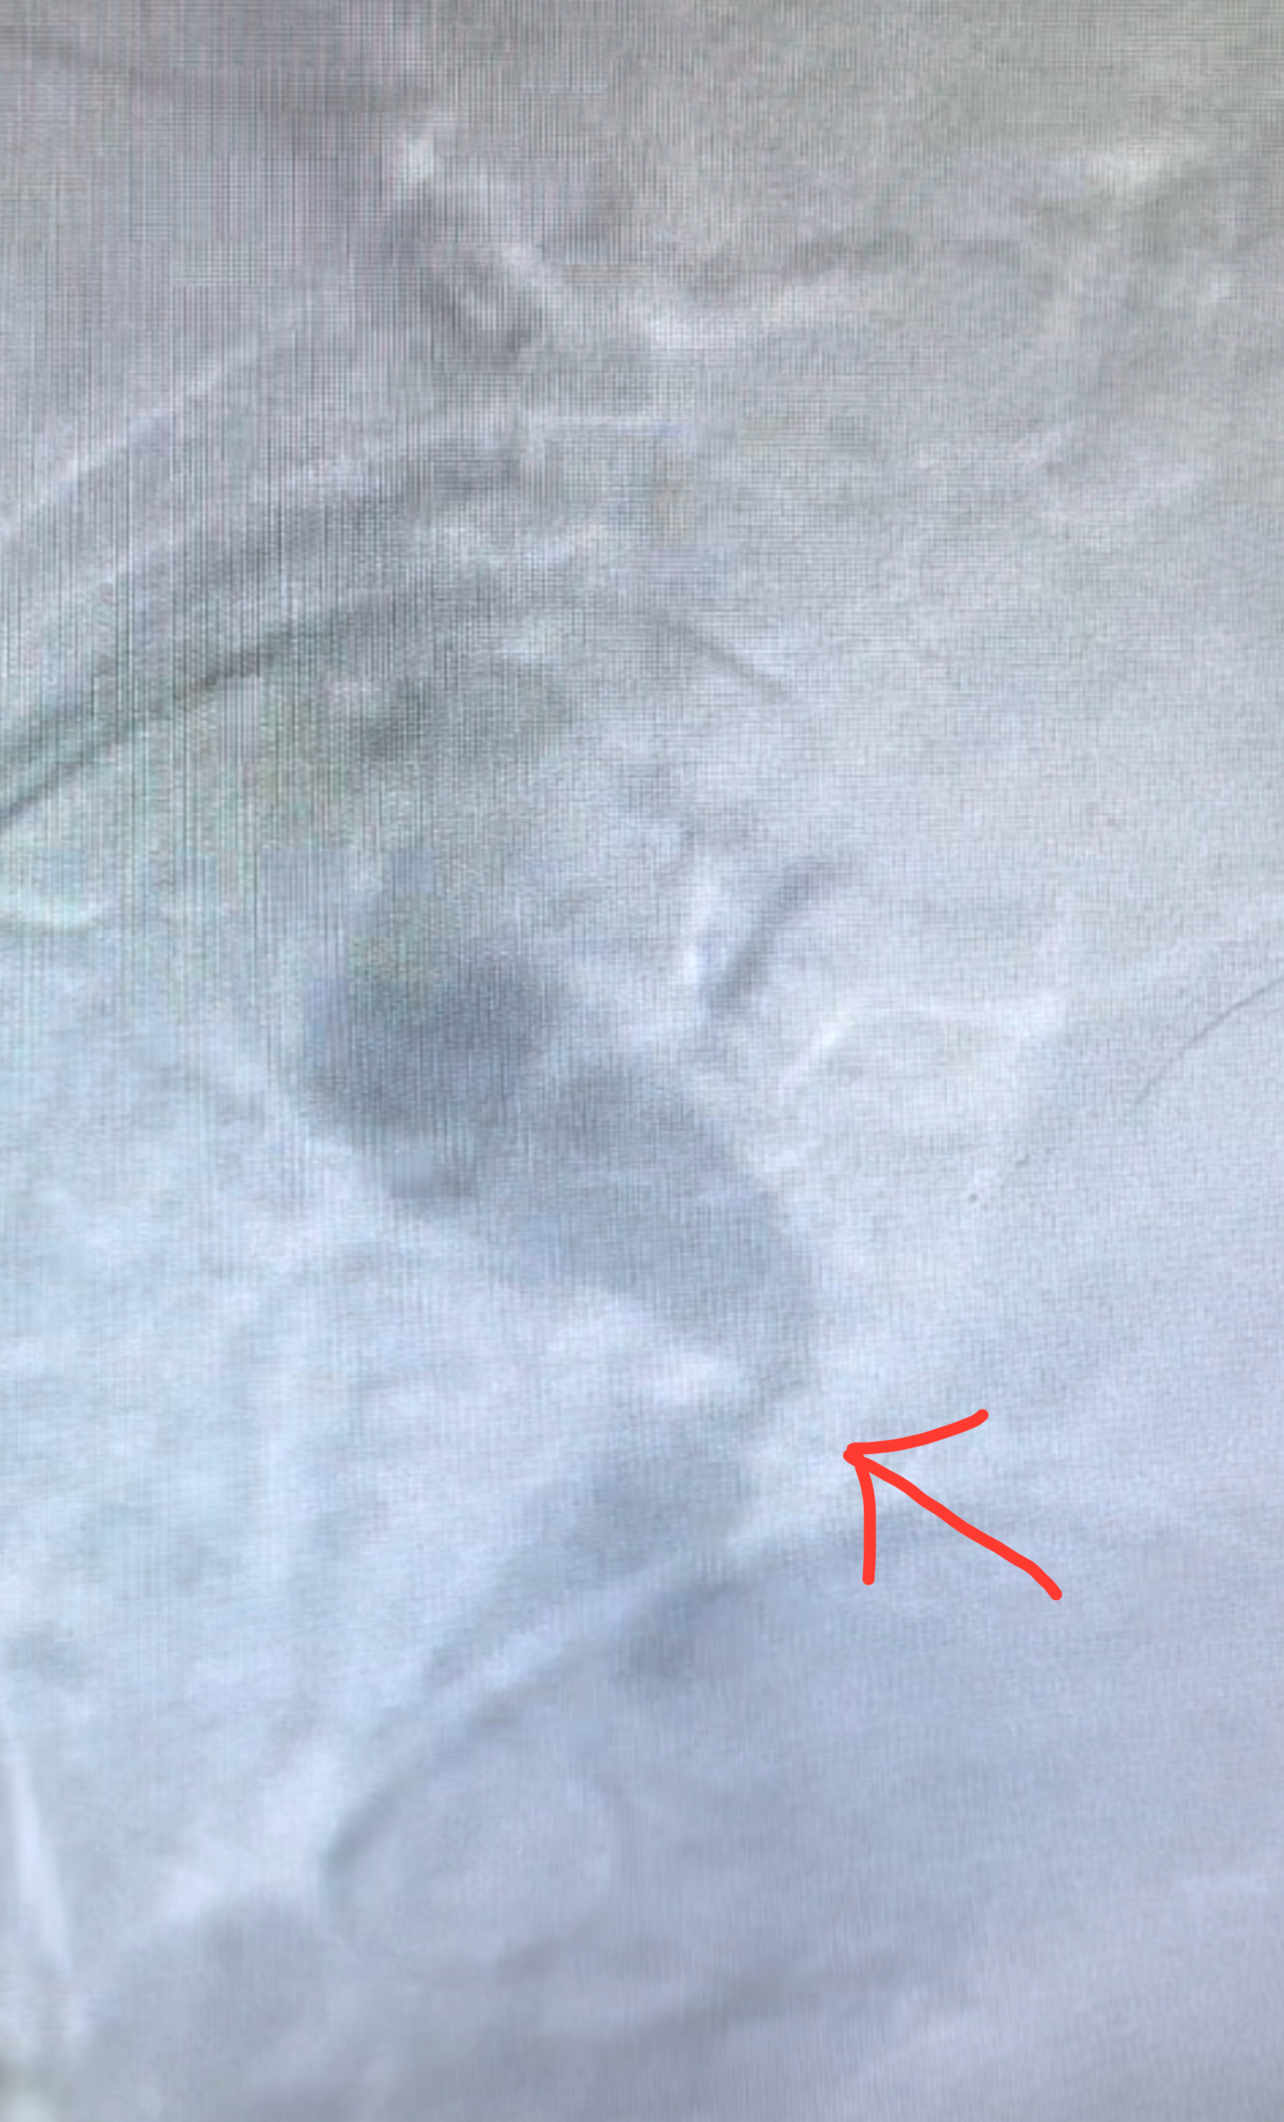

A 70-year-old female with a history of peripheral vascular disease presented with claudication in both arms, manifested as pain in both arms. Her left subclavian was stented months prior to presentation. An aortogram revealed severe stenosis of the innominate artery (Figure 1). Since multiple attempts to cross the lesion antegrade from the femoral access site were unsuccessful, we proceeded with the successful deployment of an embolic protection filter in the right internal carotid artery via our right radial artery access site (Figure 2). Using the right radial artery, we passed a long run-through guidewire into the distal abdominal aorta. Due to severe aortic tortuosity, we were unable to snare the wire from the aorta. Therefore, we upsized the radial sheath to 7 French over both wires (runthrough and bare). Using a support catheter, we exchanged the runthrough wire for a Glidewire Advantage. We advanced an 8 x 29mm balloon expandable stent to the area of innominate stenosis and deployed it (Figure 3). We postdilated the stent with a 14mm balloon. Angiography demonstrated adequate expansion. On follow up, the patient was without claudication and had triphasic flow in the innominate and left subclavian arteries.

Treating innominate artery stenosis via radial access employing a sole entry point for both embolic protection and treatment administration offers a substitute where additional access is infeasible. Modern embolic protection techniques are superior due to their flexibility and ease of use. In this case, placing the embolic protection device in the carotid artery was mandatory through the sole radial access to prevent trapping the filter behind the innominate artery stent. We were able to perform both the embolic device placement and the stenting with the same radial access.